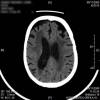

AVC amplio de territorio de A. cerebral media

Hematoma subdural por caída.